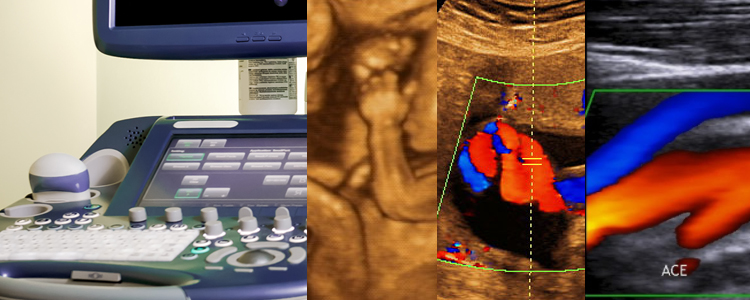

Ultrassom-Doppler colorido

O ultrassom Doppler, também conhecido como ultrassom Doppler ou ecodoppler colorido, é um exame importante para avaliar a circulação vascular e o fluxo sanguíneo de órgãos específicos ou partes do corpo humano. No caso de suspeita de estreitamento, dilatação ou oclusão dos vasos sanguíneos, o médico poderá solicitá-lo. É indicado para a avaliação de trombose, aneurisma ou veias varicosas, sendo também muito utilizado durante a gravidez para verificar so fluxo sanguíneo entre a mãe e o feto, denominado Doppler fetal. Assim como o ultrassom comum, o ultrassom Doppler é realizado por meio de equipamentos que emitem ondas sonoras que chegam ao tecido e retornam na forma de ecos, que são convertidos em imagens.